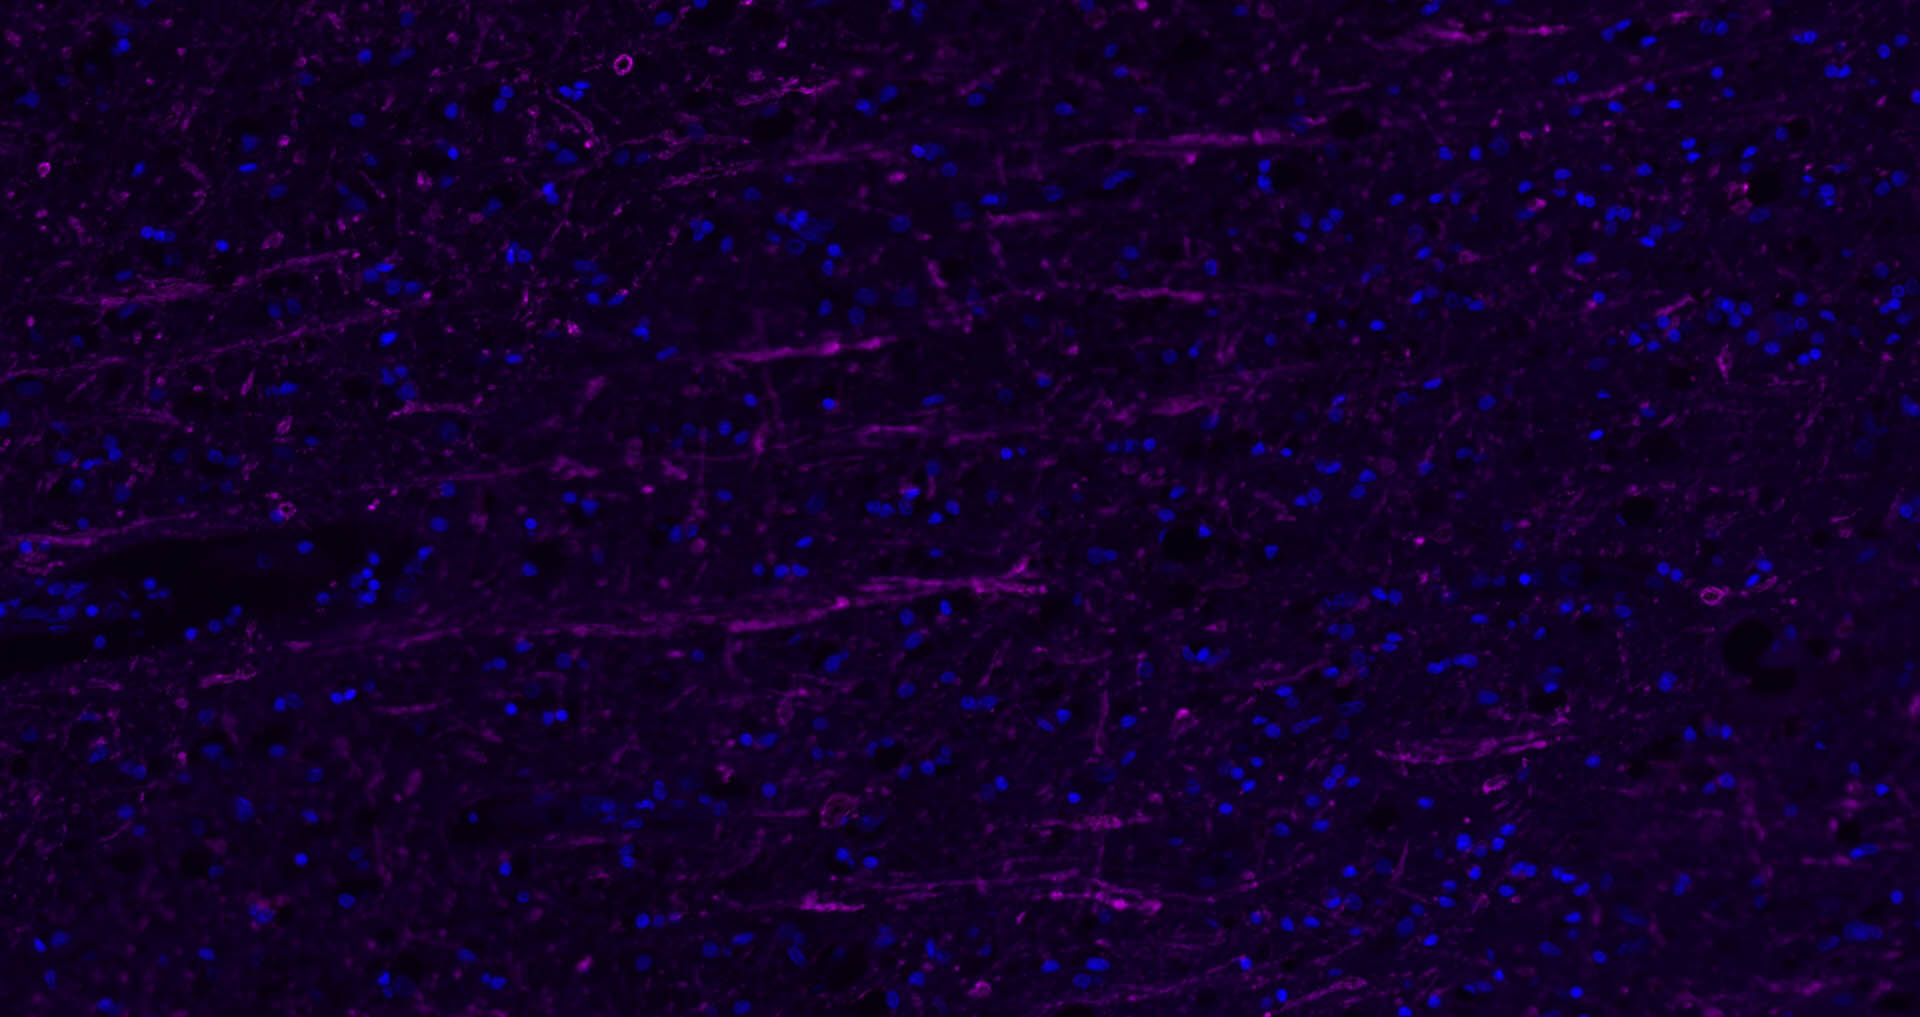

The protein encoded by the classic MBP gene is a major constituent of the myelin sheath of oligodendrocytes and Schwann cells in the nervous system. However, MBP-related transcripts are also present in the bone marrow and the immune system. These mRNAs arise from the long MBP gene (otherwise called "Golli-MBP") that contains 3 additional exons located upstream of the classic MBP exons. Alternative splicing from the Golli and the MBP transcription start sites gives rise to 2 sets of MBP-related transcripts and gene products. The Golli mRNAs contain 3 exons unique to Golli-MBP, spliced in-frame to 1 or more MBP exons. They encode hybrid proteins that have N-terminal Golli aa sequence linked to MBP aa sequence. The second family of transcripts contain only MBP exons and produce the well characterized myelin basic proteins. This complex gene structure is conserved among species suggesting that the MBP transcription unit is an integral part of the Golli transcription unit and that this arrangement is important for the function and/or regulation of these genes.

| IF | Human, Mouse, Rat | Rabbit, Pig, Sheep, Cow, Dog, Horse | 1:500-2000 |